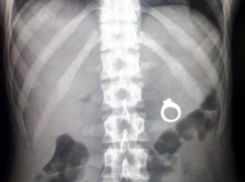

Происшествия Четырехлетний мальчик случайно проглотил кольцо в Ростове

Ребенок с инородным телом в желудке доставлен в больницу